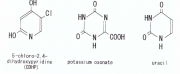

| 22:10, 28 בנובמבר 2017 | FMF1.PNG (קובץ) |  |

39 קילו־בייטים | Motyk | 1 | |